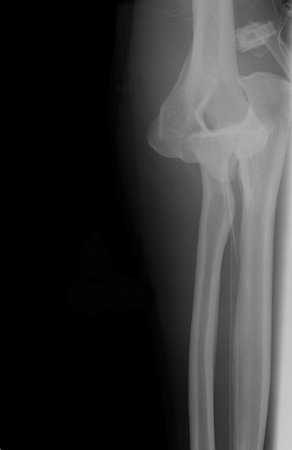

Joint dislocation

Anteroposterior x-ray view of an elbow dislocation

Personal collection of Dr Paul Novakovich